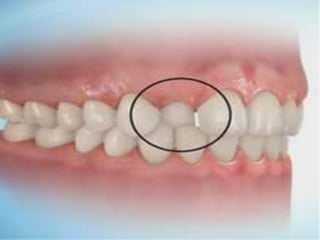

SCISSOR BITE

is present when one or more of the adjacent posterior teeth are

either positioned completely buccally or lingually to the antagonistic

teeth and exhibit a vertical overlap.

e.g: brodie syndrome, pierre robin syndrome---primary,mixed!

SCISSOR BITE is presentwhen one or more of the adjacent posterior teeth are either positioned completely buccally or lingually to the antagonistic teeth and exhibit a vertical overlap. e.g: brodie syndrome, pierre robin syndrome---primary,mixed! Chewing,muscle,normal growth of Mn.